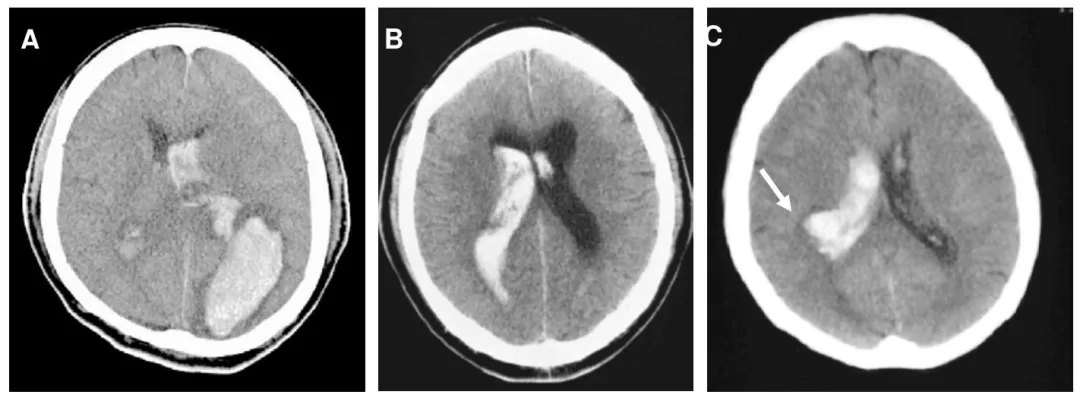

后部出血的代表性 CT 图像

A:顶叶及枕叶出血 | B:原发性脑室内出血(后部分布型)C:侧脑室后部室管膜下区出血(箭头所示)